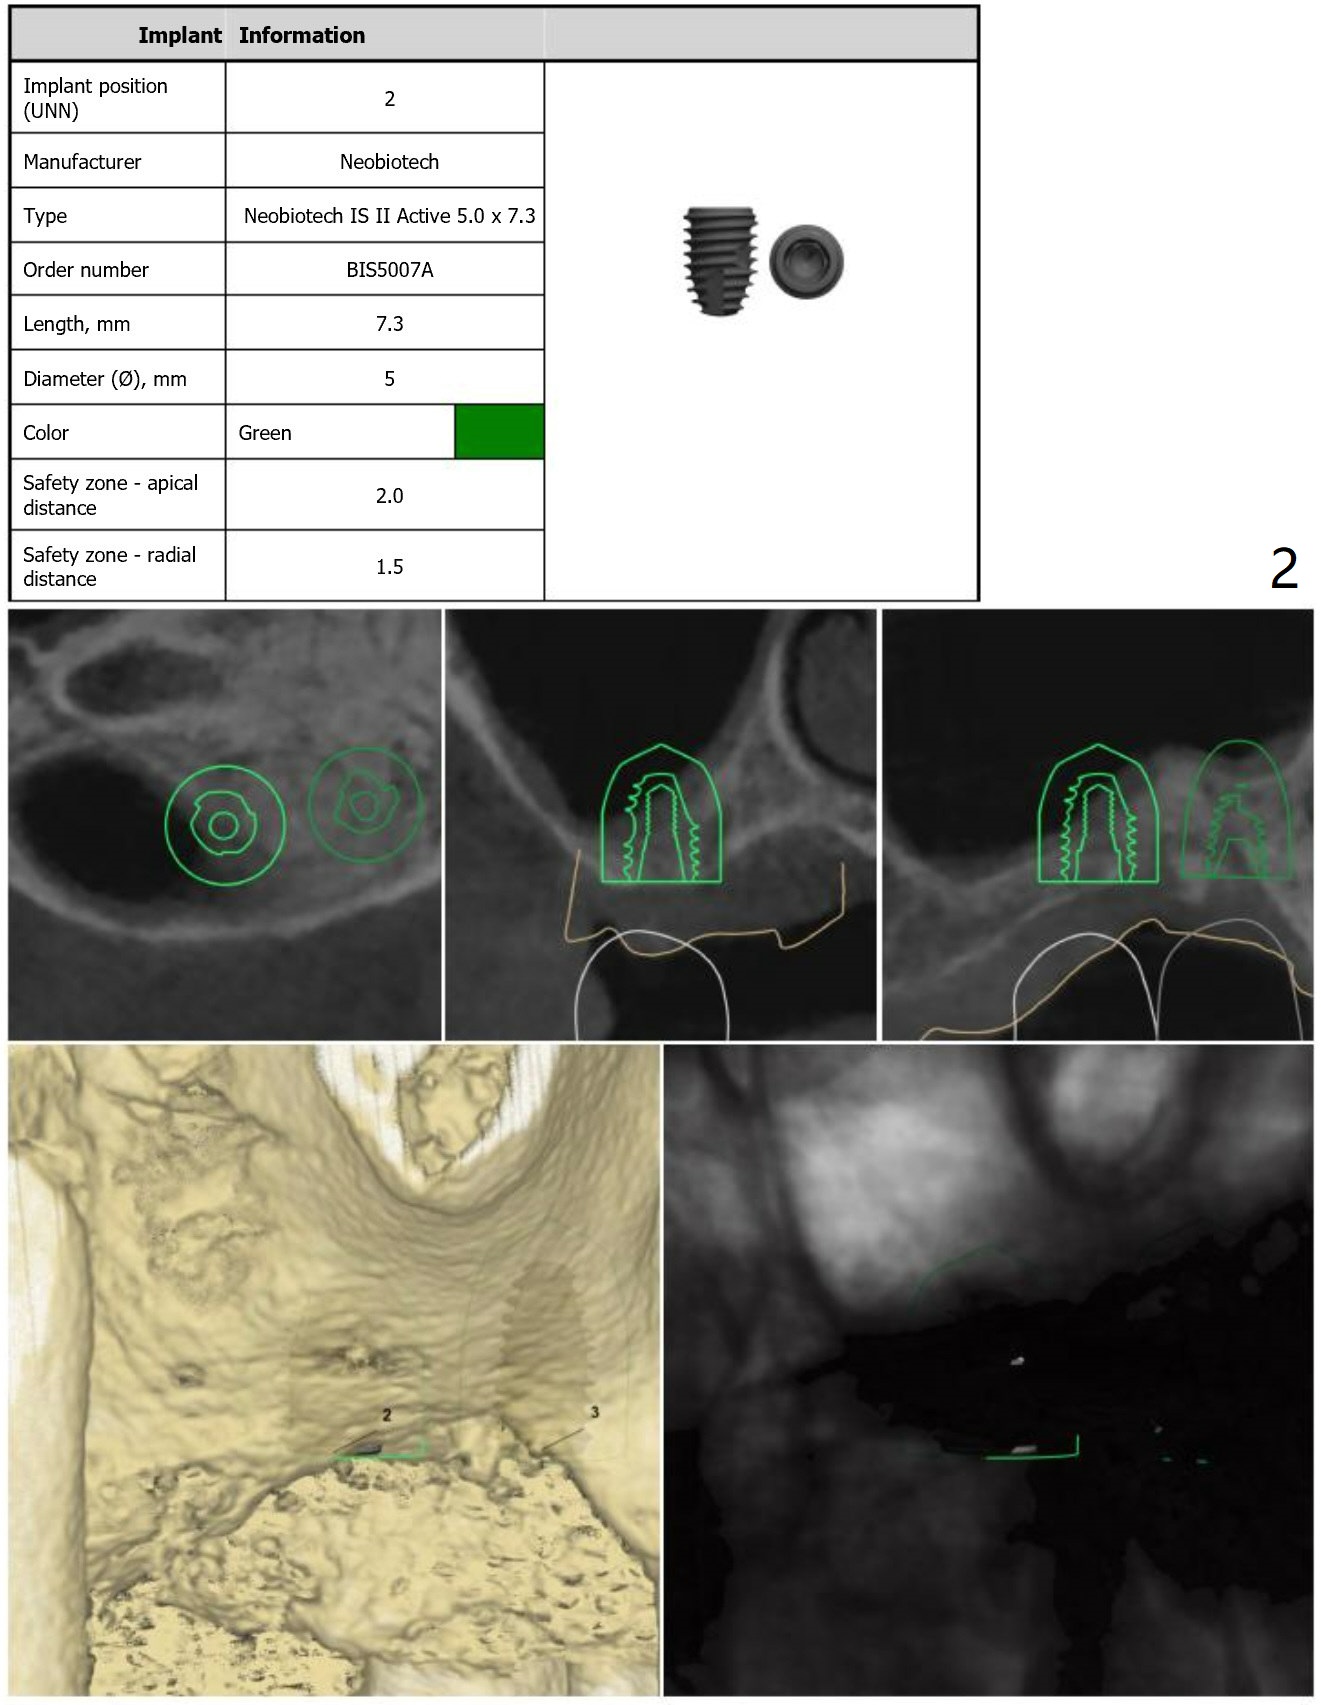

Short and Hard Bone

Return to Upper Molar Immediate Implant, Trajectory